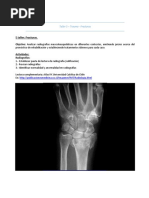

Caso N.o 1: mujer de 20 años; radiografías

anteroposterior y lateral. (A) Enfermedad de

Kienböck en estadio II y varianza cubital negativa. A

Amillo-Garayoa, S., Illescas-Talavera, J. A., & Flórez-Álvarez, F. (2005). Tratamiento quirúrgico de la enfermedad de Kienböck mediante osteotomía de acortamiento del radio distal. Revista

de Ortopedia y Traumatología, 49(2), 106–111.